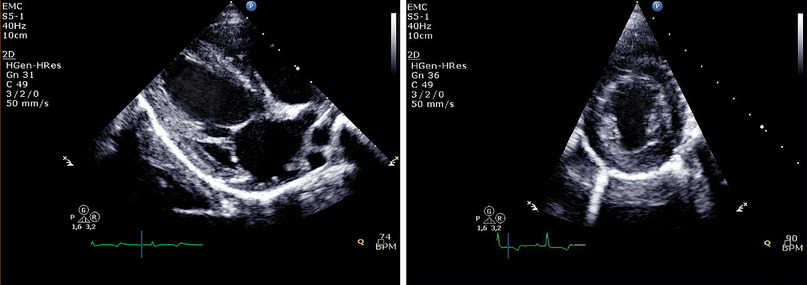

摘要:左心室舒张功能障碍是心衰患者症状的重要机制之一。本研究的目的是确定高脂饮食的糖尿病猪左心室舒张功能障碍早期征象的检测参数,使用常规和斑点追踪超声心动图。研究对象包括16头健康小型猪和18头实验诱导代谢紊乱的小型猪。在基线和3个月随访时进行超声心动图测量。两组的峰值早(E)和晚充盈速度(E/A比值)、E比值和二尖瓣环早舒张波(E/EM比值)的比值均无显著变化。在代谢紊乱组解旋速度峰值降低,对照组无变化。各组在3个月的时间点上有显著差异。总之,E/A比值和E/EM比值在代谢异常3个月后没有显著改变。因此,解旋速度峰值可作为检测左室舒张功能障碍的早期变化的一个重要标志。关键词:超声心动图 斑点追踪超声心动图 心室舒张功能障碍 糖尿病 动物模型简介:心力衰竭是发达国家的主要公共卫生问题。左心室舒张功能障碍是心力衰竭患者症状的重要机制之一,与收缩性LV功能障碍的存在或严重程度无关。二维和多普勒超声心动图可评估舒张功能障碍和充盈压。斑点追踪超声心动图可以用来量化LV力学的几个微妙的变化,例如左室扭转和解旋。当心脏的基部沿LV长轴顺时针旋转时,心尖逆时针旋转。这导致了心脏的扭动。LV解旋在力学早期左室充盈起着重要的作用。糖尿病是左室舒张功能障碍发生的重要危险因素。在以前的研究中使用斑点追踪技术检测糖尿病的LV功能障碍,包括使用小动物模型的两项研究。目前的研究的目的是确定参数,可用于检测大的代谢功能障碍的动物模型早期迹象的LV舒张功能障碍,使用常规和斑点追踪超声心动图。虽然以前的研究表明,左室舒张功能解旋可能是一个有意义的指标,其作为舒张功能障碍的早期标志的潜力尚不清楚。方法:猪代谢紊乱模型:研究对象包括16头健康小型猪(平均月龄17.8±0.8,平均体重31.1±1.6公斤)和18头代谢障碍小型猪(平均月龄17.7±0.6,平均体重31±1.3公斤)。静脉注射链脲佐菌素(25 mg/kg/天)3天(总剂量75 mg/kg)诱导糖尿病。糖尿病诱导一周后,高脂饮食(25%饱和脂肪和1%胆固醇)逐渐饲喂糖尿病猪,而对照猪继续正常饮食。猪集体饲养,自由采食,每日两次,共3个月。超声心动图:在实验前和随访三个月进行超声心动图测量。使用商用超声系统在右侧卧位得到二维灰阶谐波图像,配备宽带S5-1探头。左心房容积采用双平面面积长度公式和按体表面积计算。测定早期(E)和晚期峰值(A)充填速度、E/A比值、和E-减速时间(DT)。通过放置样品体积在心尖四腔心切面二尖瓣环侧的内侧实施组织多普勒成像。根据需要调整增益和滤波器设置以消除背景噪声。为了获得最高的组织速度,将多普勒光束与所研究结构的纵向运动之间的角度调整到最小水平。以100 mm/s的扫描速度记录二尖瓣环早期舒张波(EM)。为了评估左室心尖和基底旋转,跟踪点被自动放置可手动调整之后在舒张末期帧在每个胸骨旁短轴图像,靠近心内膜。旋转被定义为所有跟踪点的平均角位移,从顶点观察顺时针旋转表示为正值,逆时针旋转表示为负值。结论:高脂饮食的糖尿病猪血糖和血脂水平显著升高。常规超声心动图:经过3个月的代谢功能障碍E波速度明显增加(52±6 vs. 58±10厘米/秒)而对照组(54±9 vs. 53±9厘米/秒)。两组A波速度明显增加高脂肪饮食糖尿病猪(43±9 vs. 47±11 cm/s),对照组(40±7 vs. 46±10)?两组间E/A比值和E/EM比值均无明显变化。E/A比值与E/Em比值两组均未发生明显变化。斑点追踪超声心动图:3个月的代谢功能障碍明显解旋速度峰值降低,而对照组未发生变化。发现E或E / EM比和解旋速度峰值无显著相关性。高脂饮食下糖尿病猪的LV纵向和周向应变和应变率从基线到3个月没有发生显著变化。讨论:解旋速度峰值在糖尿病猪高脂肪饮食与健康的动物进行代谢功能障碍发病3个月明显下降。表明,解旋速度峰值可作为检测左室舒张功能障碍的早期变化的一个重要标志。结论:在这项研究中,基于综合常规和斑点追踪大量的代谢紊乱动物模型的左心室超声心动图分析,发现LV解旋速度峰值是左室舒张功能障碍的早期检测参数。